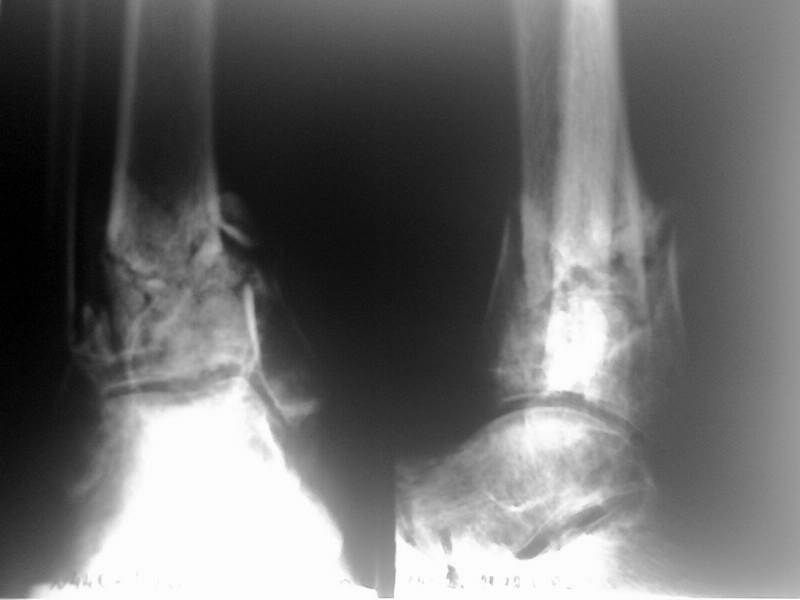

Доброго времени суток! Хотелось бы посоветоваться по срокам и тактике лечения пациента с

переломом пилона 6 месячной давности.

Пациент 50 лет, получил травму в июле 2008г. - упал с высоты 2 м, подвернул ногу. Лечился

вытяжением в соседнем отделении, через 4 недели был загипсован и отправлен восвояси. Через 3

месяца в поликлинике ему сняли гипс и заставили ходить с нагрузкой на ногу, чего он сделать не

смог - нога подворачивается, сильных болей нет. Через 6 месяцев с момента травмы пациент

сообразил, что что-то идет не так, и сам пришел к нам с вопросом - "Что делать?" При осмотре

имеется тугая подвижность в зоне перелома, движения в голеностопном суставе ограничены,

острых болей нет. Отек стопы и голени умеренный. Операция назначена на 27 января, планируем

наложение аппарата Илизарова для устранения смещения по оси и длине, затем планируется

накостный остеосинтез большеберцовой и малоберцовой. Но возникает ряд вопросов.

-Оптимальные сроки накостного остеосинтеза?

- Фиксаторы? Лист клевера и обычная пластина на малоберцовую или искать LSP?

- И совсем уж крамольный вопрос - нужен ли накостный остеосинтез для

восстановления анатомической целостности в принципе, через 7 месяцев

после травмы?